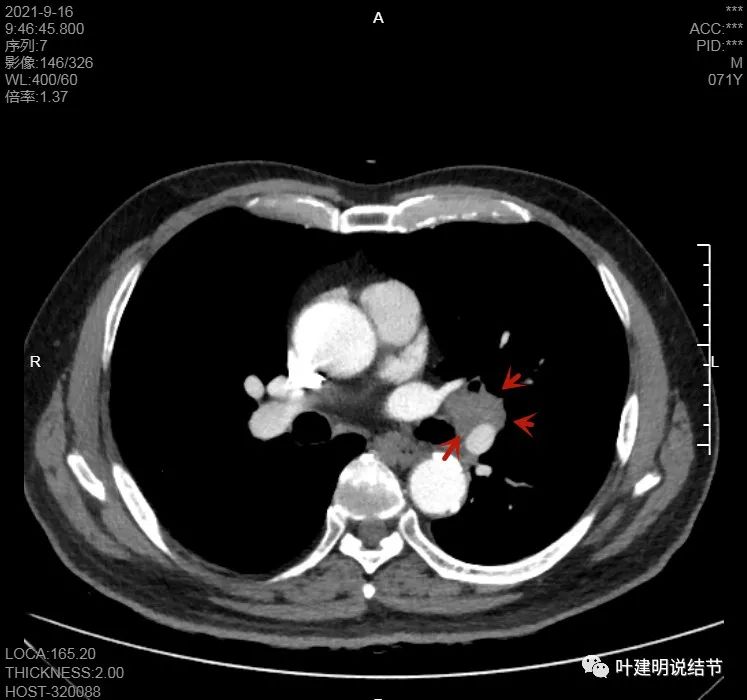

左肺门区淋巴结肿大

肺门区淋巴结挤压附近肺血管,但似乎示见肿瘤侵犯破坏血管壁

淋巴结巨大,部分包绕肺血管,但仍未见明显侵犯血管壁

肺血管受压明显,气管内壁感觉也是光滑的

以上诸图均示肿大淋巴结挤压肺血管,但未见确切侵犯破坏,支气管内壁也感觉是光滑的,没有肿瘤突向管腔